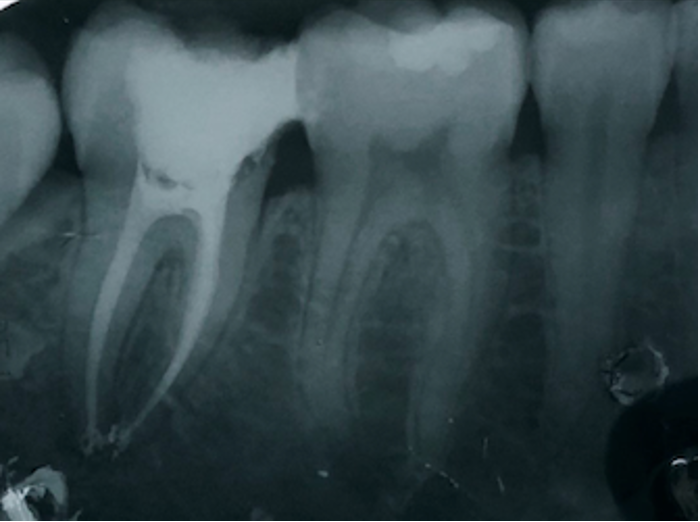

Una corretta terapia canalare con un perfetto sigillo a livello degli apici delle radici è fondamentale. I denti devitalizzati impropriamente possono creare ulteriori problemi che poi andranno a ripercuotersi sulle cure effettuate successivamente come le ricostruzioni e le corone protesiche con conseguente fallimento del piano terapeutico.

Capita spesso di incontrare denti già devitalizzati in maniera impropria che necessitano, seppur asintomatici, di essere ritrattati per evitare che i granulomi infetti visibili radiograficamente si evolvano riassorbendo tutto l’osso sottostante.